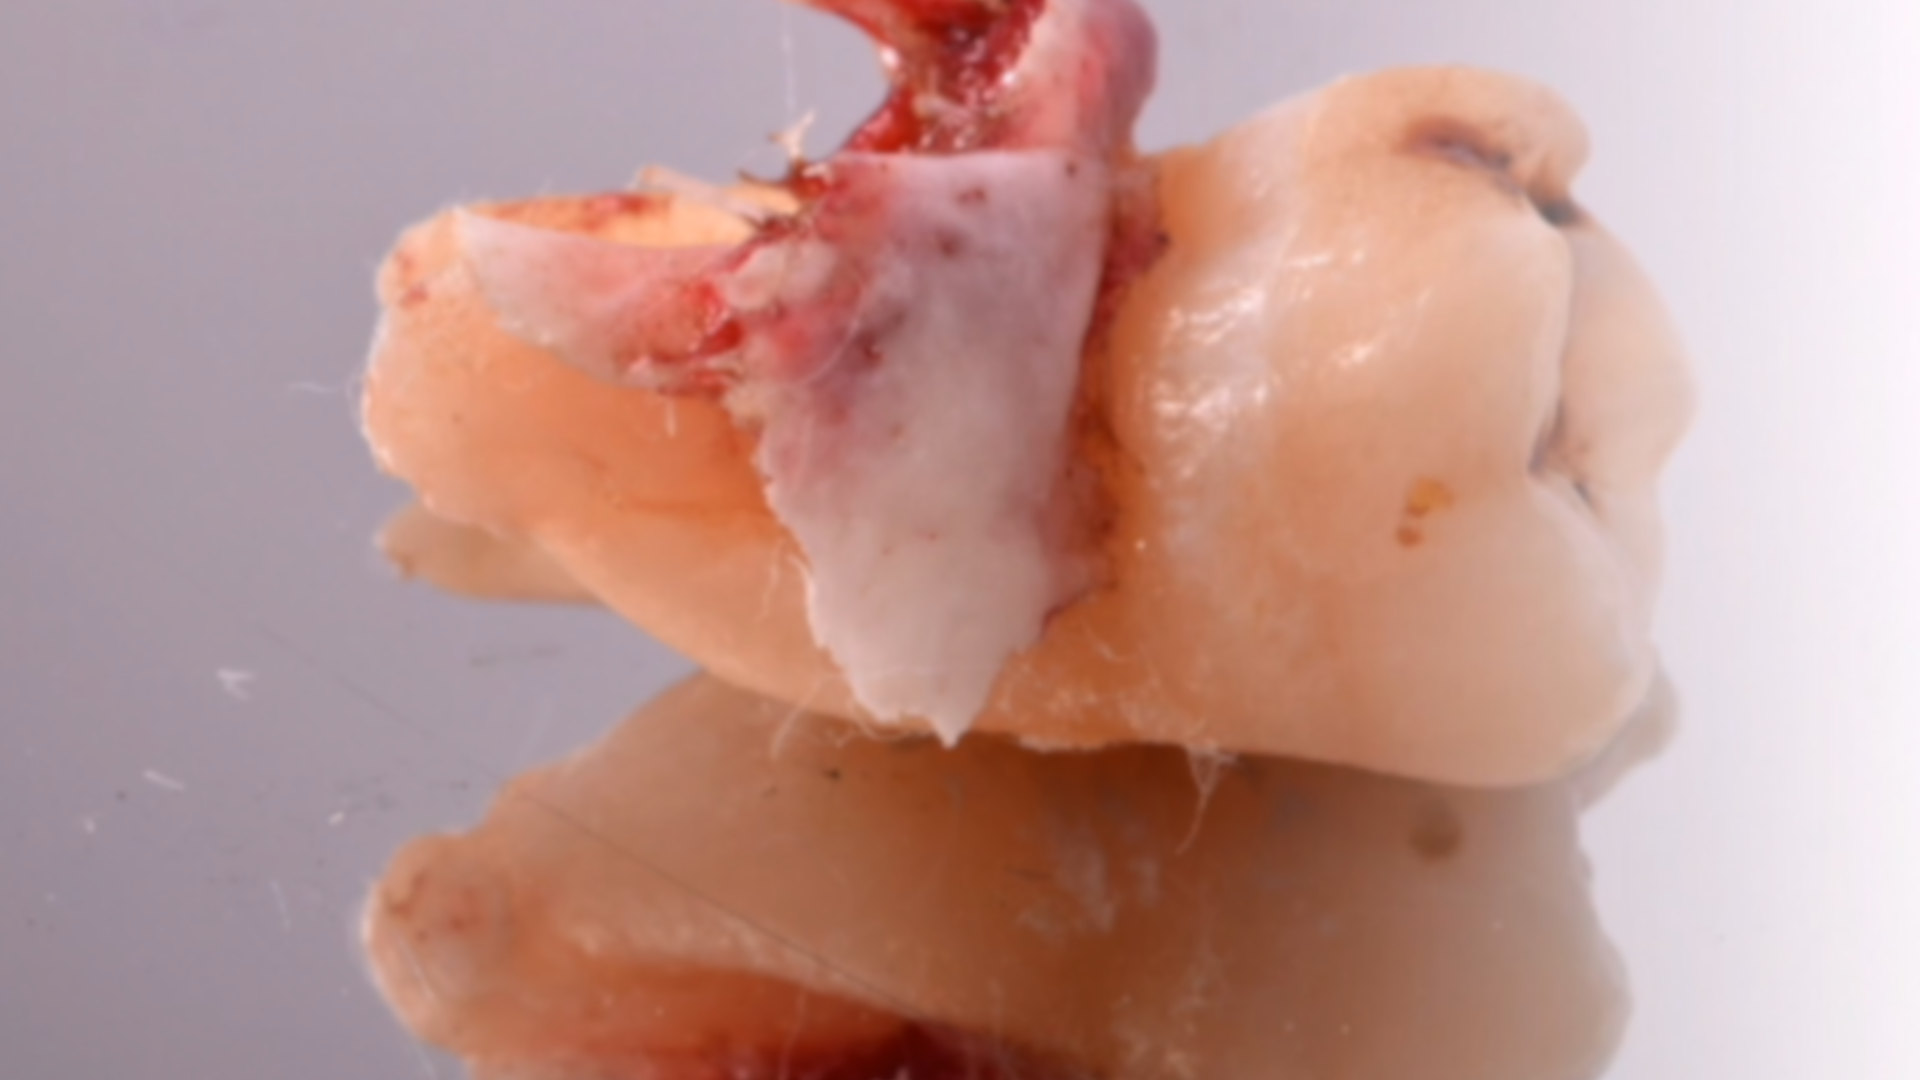

Surgical extraction of element 38: the importance of dental follicle removal